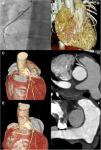

Coronary imaging, including preoperative invasive coronary angiography of the right coronary artery (A); computed tomography coronary angiography volume rendering (B and C) and multiplanar reformatting (D) and postoperative computed tomography coronary angiography volume rendering (E) and multiplanar reformatting (F). Coronary imaging revealed an anomalous origin of the non-dominant right coronary artery from the left sinus of Valsalva, with a slit-like orifice, acute takeoff and an interarterial and intramural course. Postoperative imaging confirmed corrected origin of the right coronary artery without residual stenosis.

The electrocardiogram and echocardiogram were normal. Cardiac troponin I was elevated, peaking 24 hours later at 20 515 pg/ml. Coronary angiography revealed anomalous origin of the non-dominant right coronary artery (RCA) from the left sinus of Valsalva. Computed tomography coronary angiography (CTCA) confirmed several high-risk features: slit-like orifice, acute takeoff, and interarterial and intramural course (Figure 1A-D). Cardiac magnetic resonance imaging showed absence of late gadolinium enhancement. Due to the rarity of cardiac arrest associated with non-dominant RCA abnormalities, genetic testing was carried out, which was negative for channelopathies.

The patient underwent cardiac surgery for unroofing of the RCA. He was discharged on aspirin and beta-blockers. Exercise electrocardiography performed three months later revealed no ischemia or arrhythmias. CTCA confirmed corrected origin of the RCA with no ostial stenosis (Figure 1E and F) so he was cleared to resume leisure exercise.